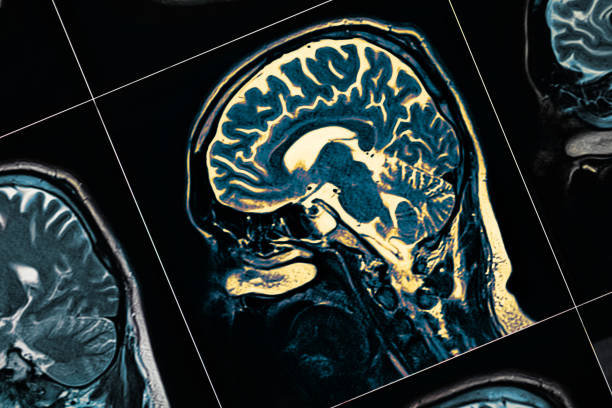

其他專家將參與為您的孩子進(jìn)行全面的體檢、 血液檢查、心理健康測試、大腦成像測試和其他檢查。它們都是找到正確診斷并制定治療計(jì)劃以幫助您的孩子控制疾病的關(guān)鍵。